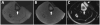

Tissues, such as bone, tendon, and ligaments, contain a high fraction of components with "short" and "ultrashort" transverse relaxation times and therefore have short mean transverse relaxation times. With conventional magnetic resonance imaging (MRI) sequences that employ relatively long echo times (TEs), there is no opportunity to encode the decaying signal of short and ultrashort T2 /T2 * tissues before it has reached zero or near zero. The clinically compatible ultrashort TE (UTE) sequence has been increasingly used to study the musculoskeletal system. This article reviews the UTE sequence as well as various modifications that have been implemented since its introduction. These modifications have been used to improve efficiency or contrast as well as provide quantitative analysis. This article reviews several clinical musculoskeletal applications of UTE.